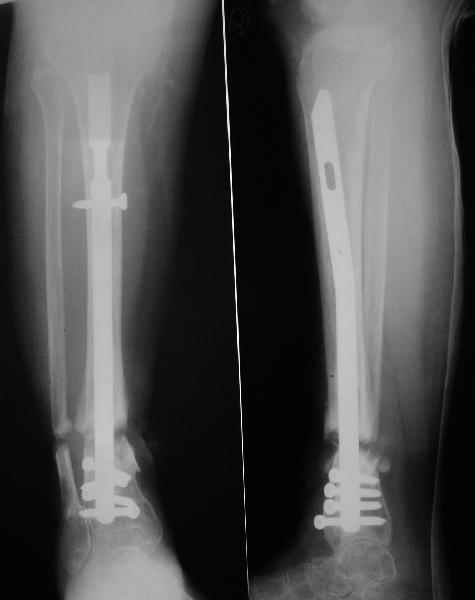

Аппарат - чтобы плавно исправить ось. В приложении - снимки на момент окончания коррекции в аппарате, фото с операции, и послеоперационная рентгенограмма.

Диаметр гвоздика 10,5 мм. Пришлось укорачивать до 23 см - уж очень миниатюрная дама, отверстия насверлил под 45 градусов, под 5 мм винты. По оси удалось сблизить до этого положения. Заперли гвоздь пока статически с планом через 2 месяца верхний винт убрать. Но это ей придется уже в Ташкенте сделать. Что скажете? Спасибо.

In attachment - x-rays at the end of alignment, the surgery, and result. The nail was cut to 23 cm. Four 45 degree holes were pre-drilled at the distal nail tip. The nail was locked statically

after some impaction. Dynamization is considered in 8 weeks. Any comments/critics?

:-)) И тебе спасибо - элегантная техника , здорово сработано.

А вдруг там все-таки от дистракции образуется регенерат, хоть дохленький? На созревание и зарезервировали 2 месяца стабилизации.

Если регенерата совсем не будет - после отпирания гвоздя отломки начнут сближаться до полного контакта. А если все-таки будет - еще и ~1 см выиграем.